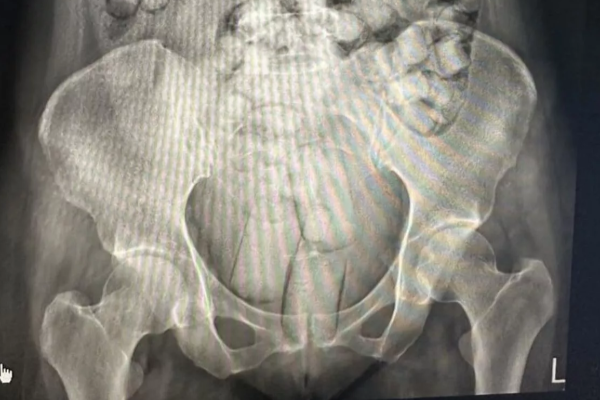

அவர்களை எக்ஸ்ரே சோதனைக்குட்படுத்தியபோது, அவர்கள் உடலுக்குள் ஏராளமான கேப்சூல்கள் இருப்பது தெரியவந்துள்ளது.

ஒரு பெண்ணின் உடலுக்குள் 54 கேப்சூல்களும் மற்ற பெண்ணின் உடலுக்குள் 61 கேப்சூல்களும் இருந்துள்ளன.

அந்தப் பெண்கள் சிறிய அளவிலான கேப்சூல்களை விழுங்கியுள்ளார்கள். பெரிய கேப்சூல்களை அவர்கள் தங்கள் ஆசனவாய் வழியாகவும், சில கேப்சூல்களை பெண்ணுறுப்புக்குள்ளும் மறைத்து கொண்டுவந்துள்ளார்கள்.